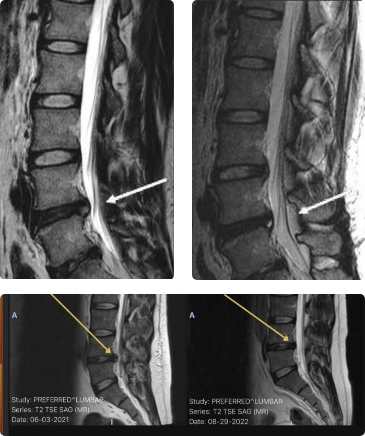

Imaging studies such as X-rays, CT scans, and MRIs provide detailed views of the spine, discs, and surrounding tissues, while advanced techniques like Magnetic Resonance Neurography (MRN), discography, myelography, ultrasound-guided testing, and bone scans/SPECT improve diagnostic accuracy, especially in complex cases.

Spine Imaging Scan Spine MRI Scan